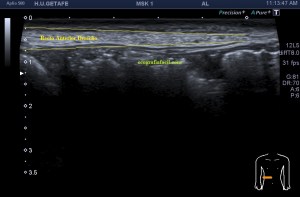

5

6

En la imagen 5 ves una estructura con un campo de escaneo limitado a la zona de interés, de derecha a izquierdo de la pantalla o de proximal a distal según la zona a estudio unos 5 cms, que es el tamaño del transductor. La anatomía de la ecoestructura perfectamente delimitada y nítida.

En la imagen 6 ves que la estructura estudiada es de casi 25 cms, sumados, donde la reconstrucción de la imagen hace que sea más pequeña y todo esté más junto de superficial a profundo, emborronándose todo o perdiendo nitidez. En la imagen 6 ves un tramo marcado con líneas amarilla finas correspondiente al mismo tramo de la imagen 5, observa tu misma la diferencia, la diferencia es sustancial. Las flechas amarilla corresponden a sombras acústicas por la sumación de la imagen unido al movimiento del operador y eventualmente a alteraciones del tejido (calcios) de la ecoarquitectura que se verán acentuados.